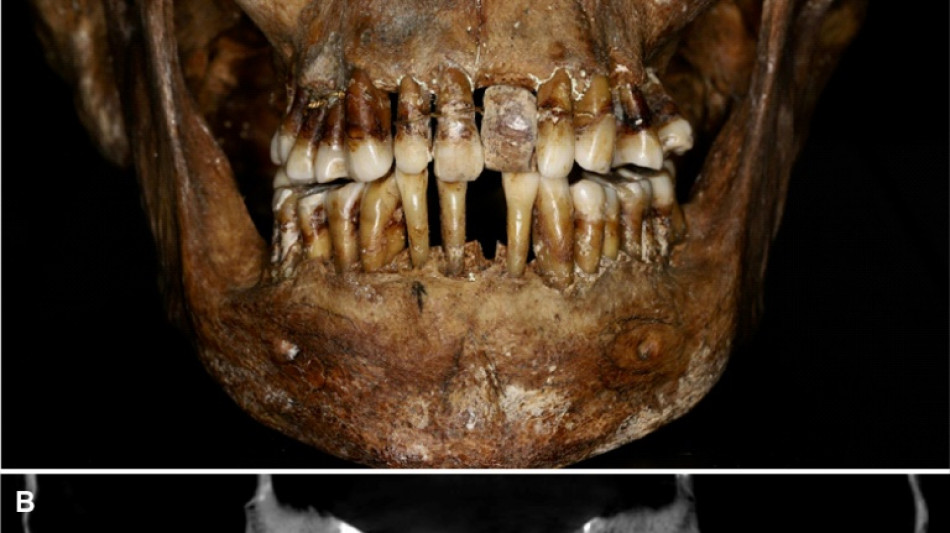

Plus de trente ans après, une équipe comprenant des archéologues et des dentistes dévoile qu'Anne d'Alègre était atteinte d'une maladie parodontale qui provoque le déchaussement progressif des dents, selon une étude parue cette semaine dans Journal of Archeological Science.

Les images radiologiques par "Cone Beam", un scanner en 3D, montrent que la patiente portait une prothèse dentaire remplaçant une incisive, soutenue par des fils d'or, ainsi qu'une ligature de contention sur des pré-molaires.

Des examens en macroscopie ont déterminé que cette prothèse était en ivoire d'éléphant, écartant la piste de l'ivoire de dents d'hippopotame, également utilisé à l'époque.

A long terme, ce traitement, ainsi que les "multiples resserrages nécessaires, ont entraîné l'instabilité des dents voisines", détaille l'Inrap.